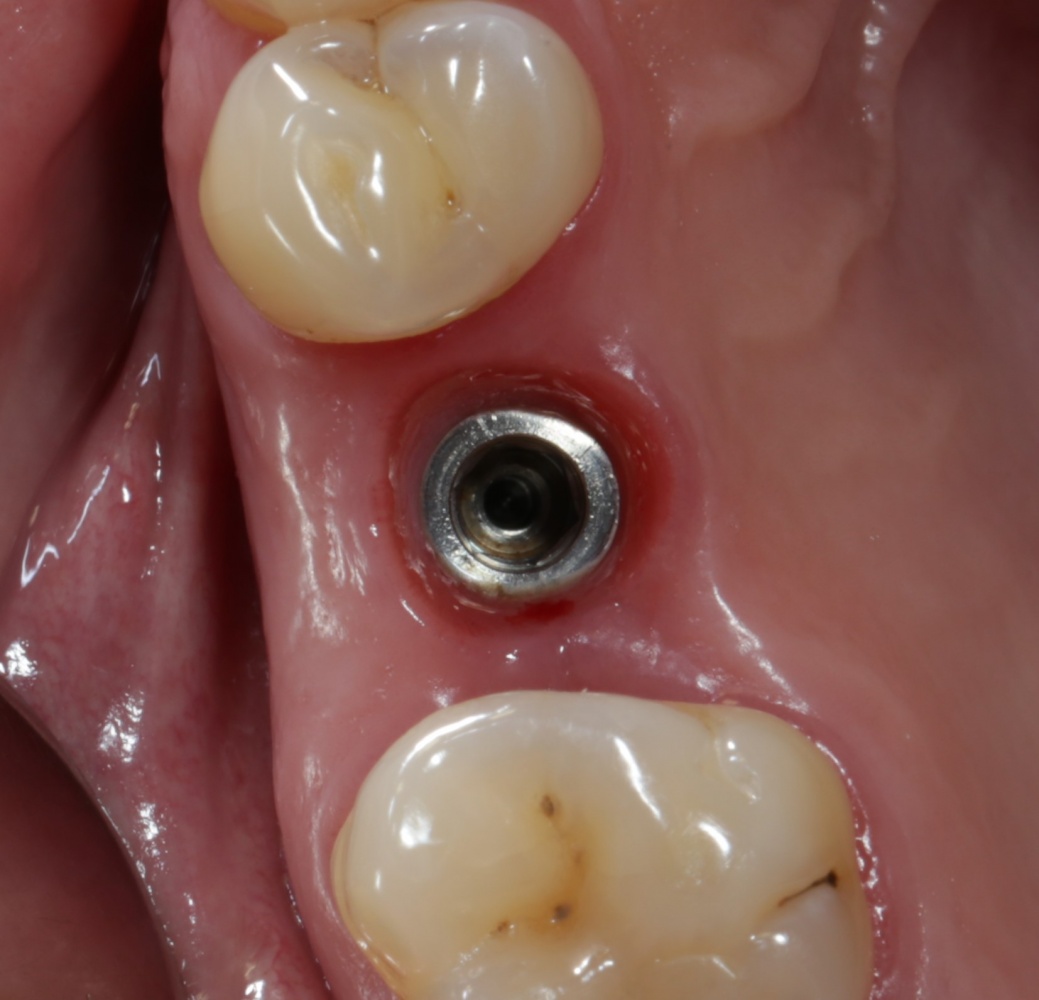

Теперь делаем разрез и открываем импланты:

A09A6620 (2) A09A6621 (2)

На фотографиях хорошо видно, какие изменения произошли с областью операции за четыре месяца. Пересаженный костный блок интегрировался настолько хорошо, что частично заросли заглушки имплантов. Такое нередко происходит, именно поэтому в подобных случаях я предпочитаю импланты с конической ортопедической платформой — их легче открывать.

Нам остается просто поставить формирователи десны:

A09A6628 (2) A09A6629 (2)

и подождать, пока вокруг них сформируется плотная слизистая оболочка. Потом мы направляем пациента к ортопеду для протезирования.